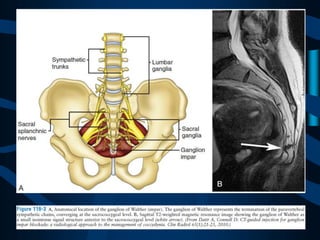

Bloqueo del Ganglio de

Walther (Impar)

INDICACIONES

EVALUACIÓN Y MANEJO DEL DOLOR PERIANAL, RECTAL Y GENITAL, SÍNDROMES

DOLOROSOS BENIGNOS COMO ENDOMETRIOSIS, DISTROFIA SIMPÁTICO REFLEJA,

PROCTALGIA, ENTERITIS POR RADIACIÓN.

ABORDAJE

PRONO